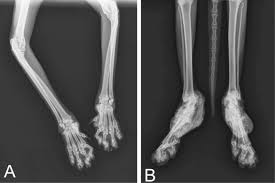

Skeletal Disease : Osteochondrodysplasia

Osteochondrodysplasia or skeletal dysplasia is the medical term for a bone development disorder. There are 7 different types of Osteochondrodysplasia, Achondroplasia, Cleidocranial dysostosis, Fibrous dysplasia, Langer-Giedion syndrome, Maffucci syndrome, Osteosclerosis,  and Osteogenesis imperfecta. These disease are similar to one another as it causes dwarfism, thinning of bones, soft tissue damage, brittle bones, etc.

The most common symptom of Osteochondrodysplasia is dwarfism, you can tell when an individual is suffering from Osteochondrodysplasia when their body composition is uneven or they physically waddle as they walk.